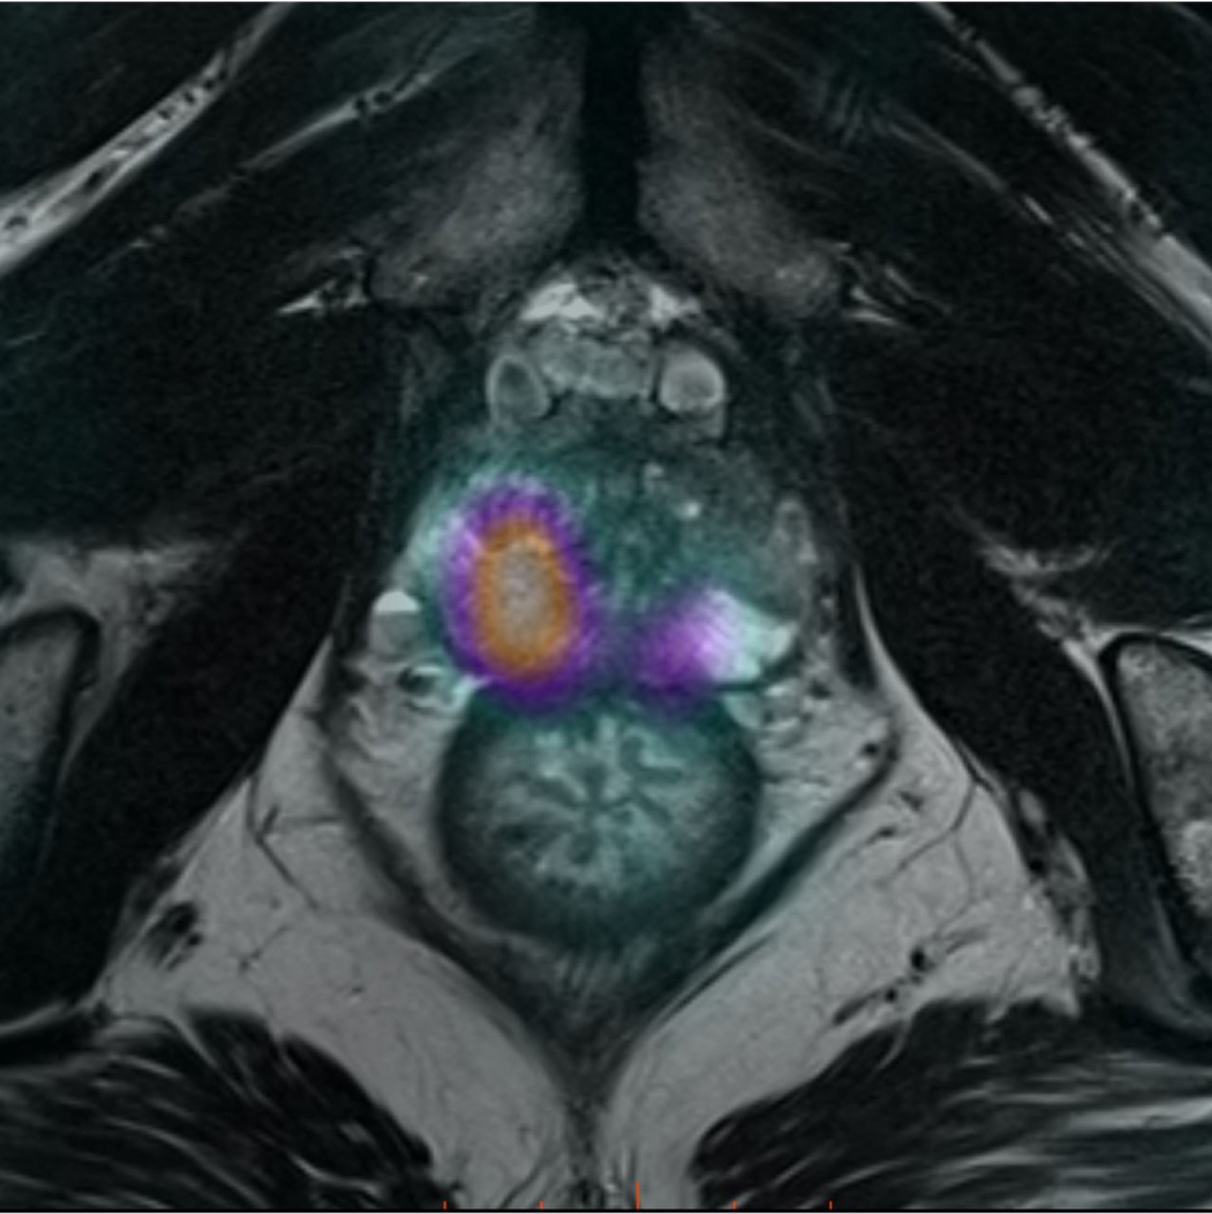

Caso condiviso da Saima Mushtaq

Paziente con anamnesi di malattia coronarica e pregresso impianto di stent sulla discendente anteriore sinistra.